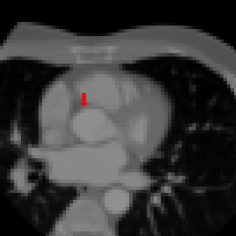

Refer to caption

(a) Original Resolution

(b) Voxel size: 1 mm

(c) Voxel size: 1.5 mm

(d) Voxel size: 3 mm

Figure 1: Axial slices from a CCTA scan, showing the right coronary ostium. The slices are shown at the original image resolution (left), resized to 1 mm (middle left), 1.5 mm (middle right) or 3 mm (right) isotropic voxels. The reference landmark location in the slices is indicated with a red arrow.